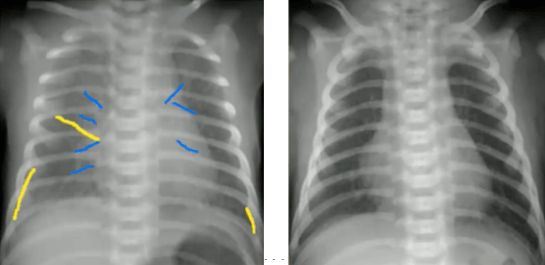

超详细胸片教学不信你还学不会

读完此文终于会看儿童胸片了

正常胸片(这 10 张经典胸片,影像医生看完都分享了)

经典胸片展示之一"正常胸片"